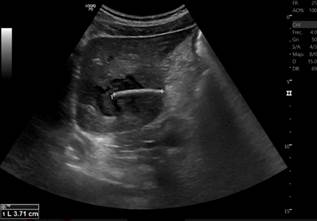

This case involves a 55-year-old male patient presenting with a one-year history of intermittent abdominal pain localized to the epigastric and left iliac fossa regions, without other associated symptoms. He denied having fever, jaundice, or ingesting any foreign body. His medical history included obesity, hypertension, and frequent alcohol consumption. He presented to our institution for an abdominal ultrasound, which identified a liver abscess in segments II and III containing a foreign body, along with inflammatory changes in the fat of the gastrohepatic omentum (Figure 1). Subsequently, an abdominal CT scan was requested to confirm these findings (Figure 2). The general surgery team opted for hospitalization to provide antibiotic therapy with intravenous ciprofloxacin 200 mg every 12 hours and metronidazole 500 mg every 8 hours. Admission laboratory tests indicated elevated acute-phase reactants (leukocytosis, mild neutrophilia, and C-reactive protein [CRP]), mild alteration in liver enzymes (aspartate aminotransferase [AST]: 52.3 U/L and alanine aminotransferase [ALT]: 23.3 U/L), with bilirubin levels, alkaline phosphatase, and coagulation times within normal limits.